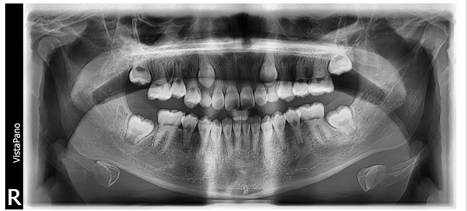

Figura 9. Análisis radiográfico

Al análisis radiográfico observamos un paciente en dentición mixta. Las piezas deciduas en su proceso fisiológico normal de reabsorción radicular.

Figura 10. Radiografías periapicales

Se observa a mayor detalle la obliteración de los conductos radiculares en las piezas permanentes, hallazgo radiográfico común en pacientes con amelogénesis imperfecta.

Figura 19. Radiografía Panorámica

En la radiografía panorámica final se observa la evaluación normal de todos los dientes permanentes.